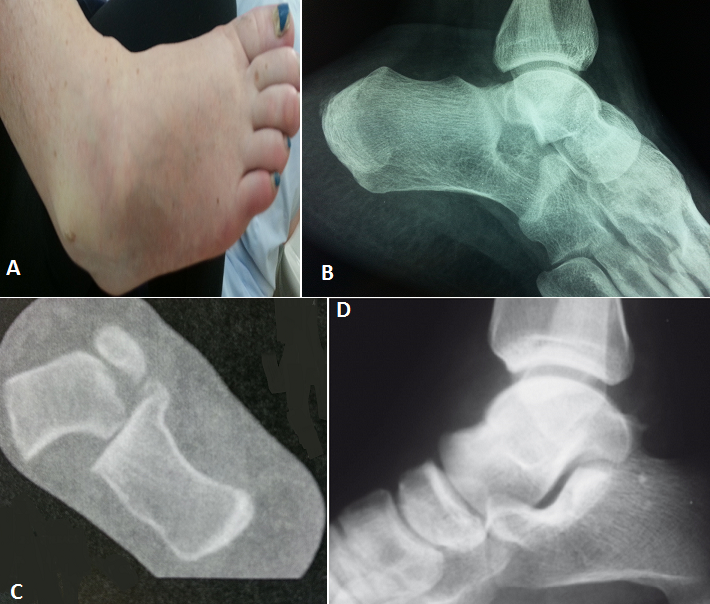

La luxation sous talienne est une perte de rapports anatomiques entre l'astragale, calcanéum et scaphoïde. C'est une lésion rare, elle représente 1% de toutes les luxations observées en traumatologie. Nous rapportons le cas d'une patiente de 40 ans, sans antécédents, ayant subi un traumatisme de son pied droit lors de la réception d'un saut d'un lieu élevé d'un mètre (mécanisme en inversion du pied bloqué en équin). Le diagnostic était évident cliniquement devant la déformation douloureuse du pied avec impotence fonctionnelle : le talon est déplacé médialement par rapport à la jambe, le pied étant en inversion, flexion plantaire et adduction avec raccourcissement du bord médial du pied et tension cutanée. Il n'y avait pas d'ouverture cutanée et l'examen vasculo-nerveux était normal. Le bilan radiographique initial avait objectivé cette luxation sous-talienne interne pure sans fractures associées. Le scanner du pied et de la cheville a confirmé ces lésions. La réduction orthopédique urgente par manoeuvres externes, a été faite dans l'heure suivant le traumatisme au bloc opératoire sous rachianesthésie et sous contrôle fluoroscopique. Après réduction, l'articulation talo-crurale était stable et le contrôle radiologique a objectivé une bonne congruence articulaire. Une contention complémentaire par botte plâtrée a été réalisée et maintenue pendant 6 semaines sans appui, puis la rééducation a été entreprise. L'évolution a été favorable, le résultat fonctionnel est très bon après un recul de 24 mois.